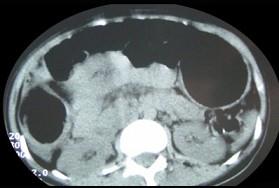

问题 女,30岁,便秘、腹痛腹胀多年,CT检查如图,最可能的诊断是 ( )

选项 A、结肠肠扭转 B、结肠肠栓塞 C、先天性巨结肠 D、结肠肠套叠 E、结肠肠梗阻

答案 C